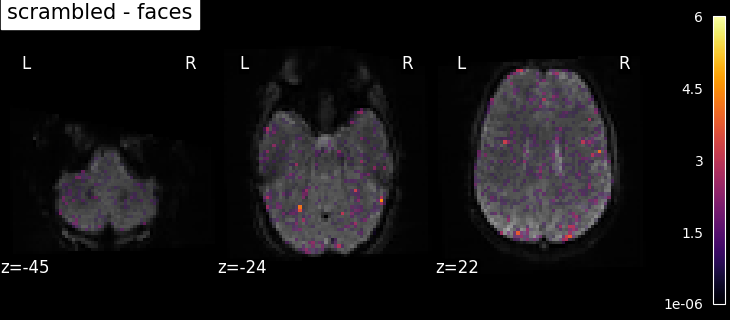

8.2.3.1. Computing contrasts¶

To get more interesting results out of the GLM model, contrasts can be computed between regressors of interest.

The nilearn.glm.first_level.FirstLevelModel.compute_contrast function can be used for that. First,

the contrasts of interest must be defined. In the spm_multimodal_fmri dataset referenced above, subjects are

presented with ‘normal’ and ‘scrambled’ faces. The basic contrasts that can be constructed are the main effects

of ‘normal faces’ and ‘scrambled faces’. Once the basic_contrasts have been set up, we can construct more

interesting contrasts like ‘normal faces - scrambled faces’.

And finally we can compute the contrasts using the compute_contrast function. Refer to Single-subject data (two runs) in native space for the full example.

The activation maps from these 3 contrasts is presented below: